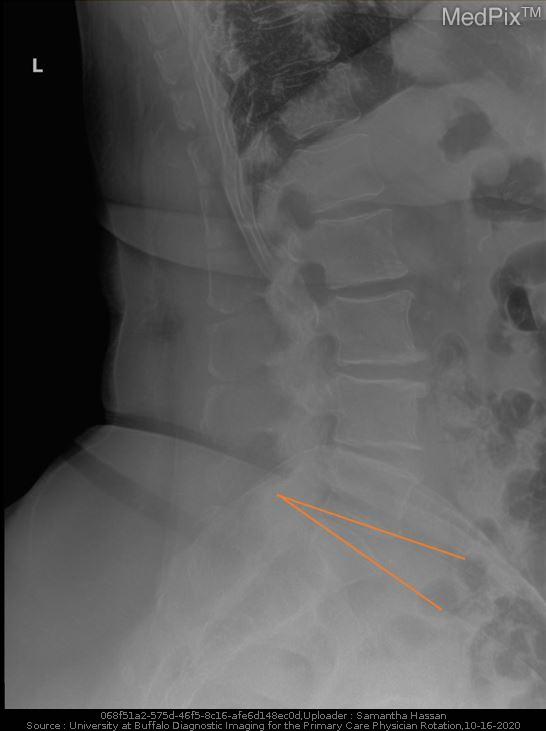

Lordosis is an excessive inward curvature of the spine. There is normally a natural inward curve in the cervical and lumbar spine but an excessive curve (especially in the low back) may lead to swayback. Increased or decreased lordosis (flat back) can affect the spine by decreasing shock absorption which decreases the distribution of mechanical stress. Physical therapy can help through education in proper posture, exercises to strengthen muscles and address other contributing factors.